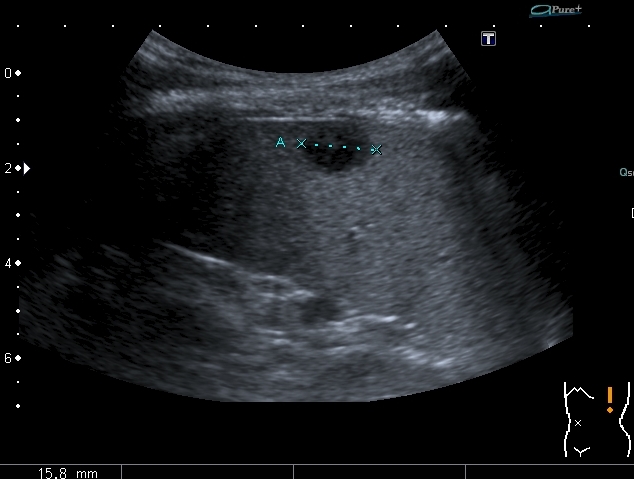

"Плохой"  подмышечный лимфатический узел, но справа. "Bad" axillar LN is seen

Hypoechoic lesions in the spleen. В селезёнке - множественные гипоэхогенные образования

При более подробном анализе случая действительно есть плюсы за болезнь Ходжкина:

1. Очаги в селезёнке

2. Распространённая лимфаденопатия, хотя "плохим" выглядит только лимфатический узел справа в подмышечной впадине, но есть лимфатические узлы до 12 - 15 мм и в левой подмышечной области , и подчелюстные лимфатические узлы

3. Перекрёстные изменения - опухоль на ребере слева - плохой лимфатический узел справа.